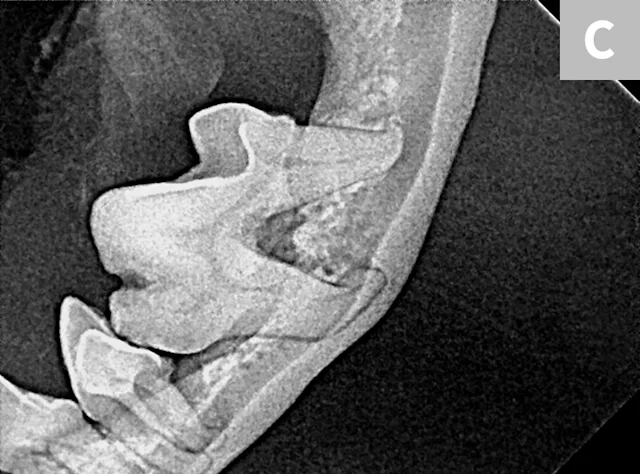

Iatrogenic fracture of the left rostral mandible after extraction of the left mandibular canine tooth (A; arrows). Same patient with iatrogenic jaw fracture after extraction (B); significant bone loss from periodontal disease was present, which contributed to this complication. Dilacerated root of the left mandibular first molar in a small-breed dog (C). The first molar in these breeds is often very large as compared with the width of the mandible. The hook on the mesial root can make extraction more challenging.

Small-breed dogs have a high first molar:mandibular height ratio, which increases the risk for fracture in cases of periodontal disease.14 In such cases, the roots can also be dilacerated (ie, there is an abnormal bend, hook, or overall shape to the root[s]); the tooth may have significant bone loss and appear to be an easy extraction, but the hook on the end of the root tip often makes removal much more difficult (Figure 6C).